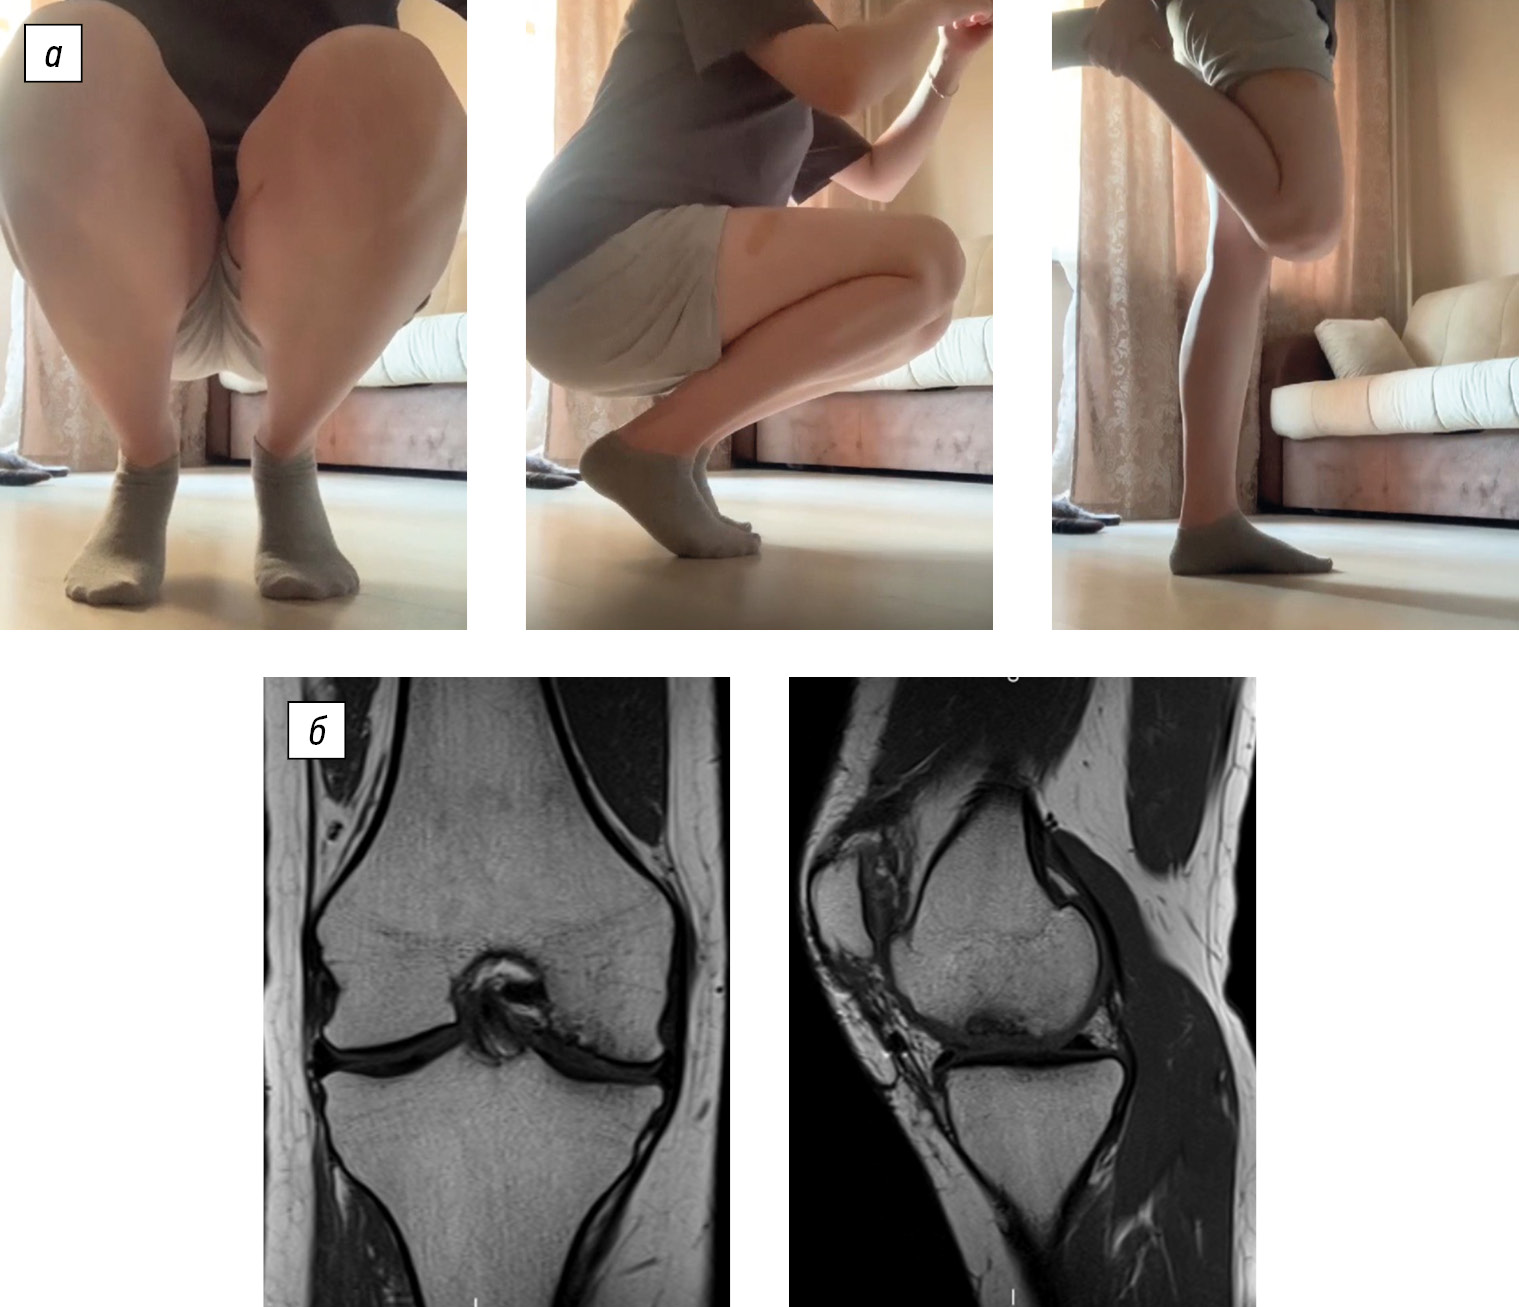

Radiographic evaluations—including X-ray, spiral computed tomography, and magnetic resonance imaging—identified an osteochondral defect in the central region of the medial femoral condyle, measuring 2.0 × 1.4 × 1.0 cm. The lesion was classified as a deep defect (ICRS grade IV). Postoperative changes were recorded, accompanied by synovitis of the right knee joint and early signs of secondary deforming osteoarthritis (stages I–II) (Fig. 1).

Fig. 1. Diagnostic imaging of patient B (age: 17 years at admission): a, X-ray of the right knee joint in anteroposterior and axial views; b, computed tomography scans exhibiting frontal, sagittal, and axial slices through the lesion; c, magnetic resonance imaging scans, frontal and sagittal views through the lesion. The area of destruction is indicated by an arrow.

Clinical evaluation was performed 2.5 years after the surgery. The patient reported no active complaints. She experienced occasional pain in the right knee joint after prolonged walking (for more than 2–3 km). The range of motion in the knee was full and painless. Functional scores: Lysholm, 92 points; KSS, 95 points (Fig. 4).

Fig. 4. Follow-up clinical and imaging evaluation of patient B at 2.5 years after reconstruction: a, range of motion in the right knee joint; b, magnetic resonance images in the frontal and sagittal planes.